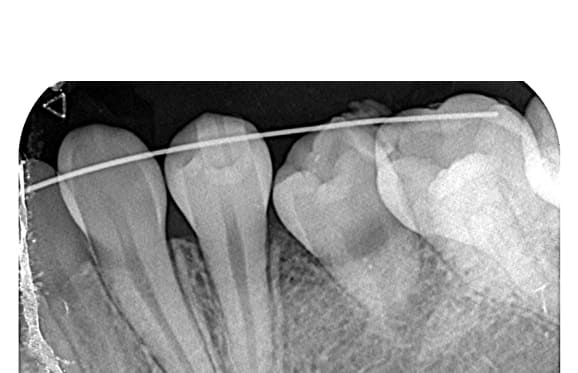

● 症例2

藤沢デンタルオフィスの破折ファイル除去

01 右上の頬側根に手用ファイルの破折

02 ファイル除去時

※若干の打診痛あり

03 最終の根充剤を充填